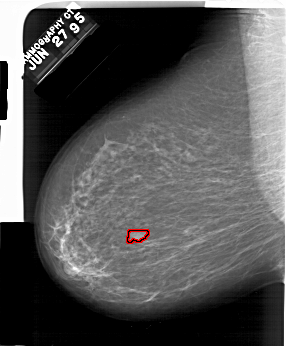

FILE: A_1554_1.LEFT_MLO.OVERLAY

TOTAL_ABNORMALITIES 1

ABNORMALITY 1

LESION_TYPE MASS SHAPE OVAL MARGINS OBSCURED

ASSESSMENT 4

SUBTLETY 4

PATHOLOGY BENIGN

TOTAL_OUTLINES 1

BOUNDARY